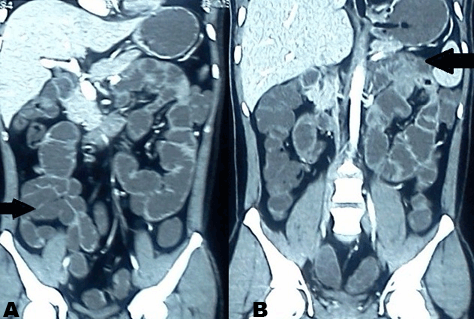

A 28-year-old male presented with generalized abdominal pain, fever and multiple episodes of vomiting. Abdominal pain was episodic and colicky and vomitus was bilious. There was no past history of trauma or surgery. Patient had a past history of three episodes of similar abdominal pain and vomiting three months back. Second episode occurred 12 days after the first episode and third episode occurred 21 days after first episode. Patient was diagnosed as a case of recurrent sub-acute intestinal obstruction by small gut stricture which was confirmed on the barium study at that time. During and after each episode the patient was managed conservatively without any surgical intervention. General physical examination during current episode showed dehydrated appearence, pulse 96/min, blood pressure 110/70 mmHg, and temperature of 99oC. Systemic examination was normal. Abdominal examination revealed distended abdomen, diffuse tenderness and a high pitch bowel sounds. Laboratory parameters were normal. X-ray of abdomen showed multiple air fluid levels. Computed tomography scan of the abdomen revealed conglomeration of gut in a thin sac suggestive of peritoneal encapsulation on the right side. There was displacement of inferior mesenteric vein and the entrapped bowel in left upper abdomen (left paraduodenal hernia). (Figure 1A–B) Gut loops were dilated and had thick walls. Exploratory laparotomy revealed encasement of bowel loops in membrane, typical of peritoneal encapsulation with inter-loop adhesions present in the bowel outside the peritoneal sac. (Figure 2) Gut inside peritoneal encapsulation was dilated, which was suggestive of obstruction. Malrotations of small gut loops was seen. After careful dissection of the membrane, adhesiolysis and release of omental adhesions, a vessel lying on ileal loops, outside the retroperitoneum, was seen which was identified as inferior mesenteric vein (IMV). (Figure 3A-B) The bowel proximal to the abnormally placed IMV was dilated with thickened wall which was suggestive of obstruction. This abnormally lying IMV was constrained by adhesions to small bowel. Peritoneal encapsulation and retroperitonealization of IMV were leading to sub-acute intestinal obstruction. Further exploration revealed a loop of intestine impacted in a left paraduodenal fossa. Diagnosis of the left paraduodenal hernia was confirmed. (Figure 4A-B) Incarcerated segment of bowel in left paraduodenal fossa had signs of strangulation with thickened walls leading to acute abdomen. Resection of incarcerated segment and the closure of hernial orifice was done. Retroperitonealization of anteriorly placed IMV was achieved. Postoperative period was uneventful and patient was discharged after one week. Patient is well on follow up for last 13 months.

Figure 1: (A-B) Computed tomography scan of the abdomen in axial and coronal cuts demonstrating left paraduodenal hernia. Arrows are outlining the hernial sac, with clustered, sharply circumscribed loops of small bowel in the left upper abdomen. In right lower abdomen gut loops conglomerated in peritoneal sac.